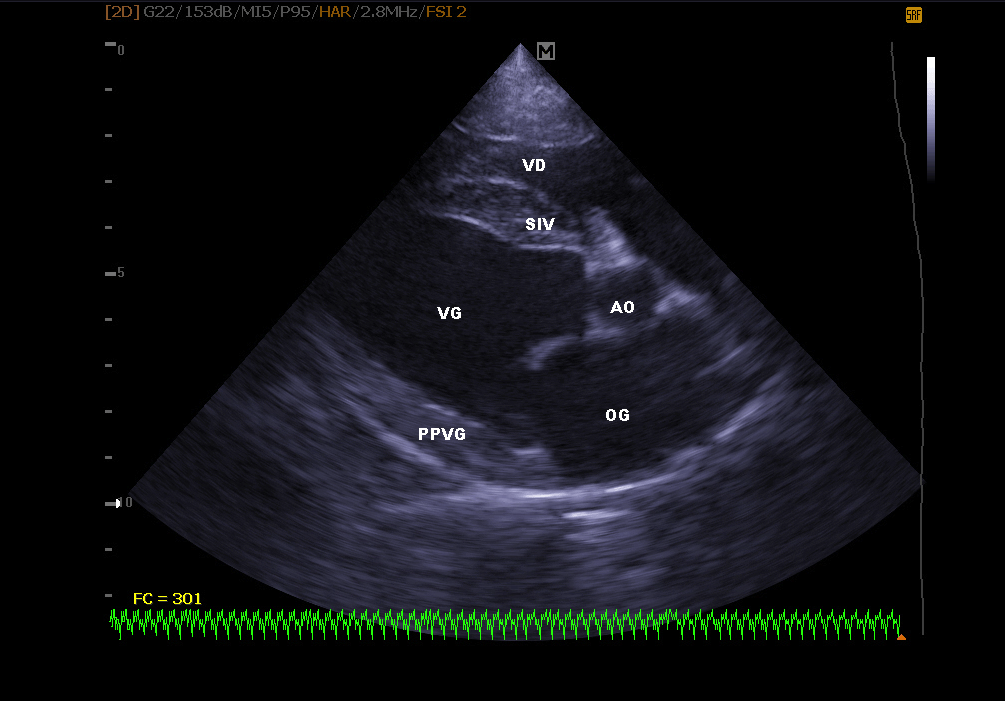

Echokardiographie:

Es ermöglicht die Visualisierung der verschiedenen Teile des Herzens (Wände, Hohlräume, Klappen) und die Identifizierung von Anomalien, die eine korrekte Herzfunktion verhindern. Bei Herzinsuffizienz ermöglicht die Echokardiographie auch eine regelmäßige Überwachung der Herzmorphologie. Es ist dann einfacher, die Behandlung an Ort und Stelle neu einzustellen.